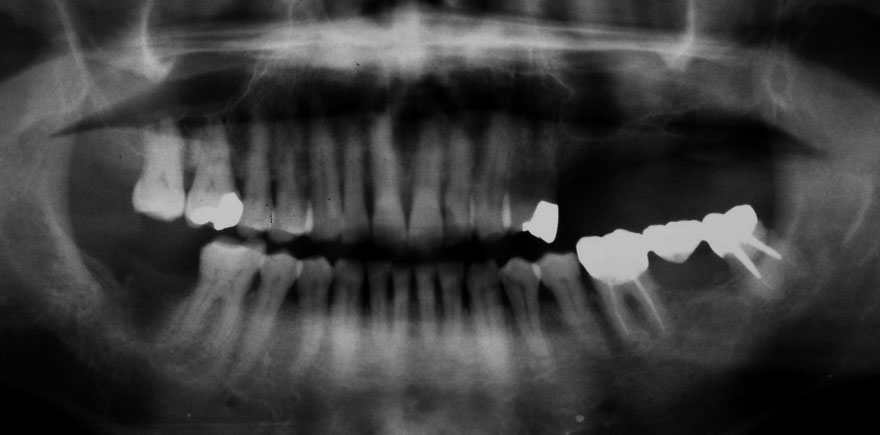

初診時 41歳 男性 平均歯槽骨喪失量:4.11mm

30年後 71歳

平均歯槽骨喪失量:3.70mm

30年間再生量:+0.41mm

年間再生速度:+0.014mm

(ケア頻度:1.27ヵ月ごと)